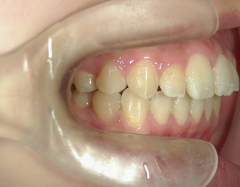

矯正歯科 治療後矯正歯科 プチワイヤー矯正 治療後矯正歯科(プチワイヤー矯正)治療後

矯正歯科 治療後

no.8_8495_治療後_左.jpgno.8_8495_治療後_正面.jpgno.8_8495_治療後_右.jpg